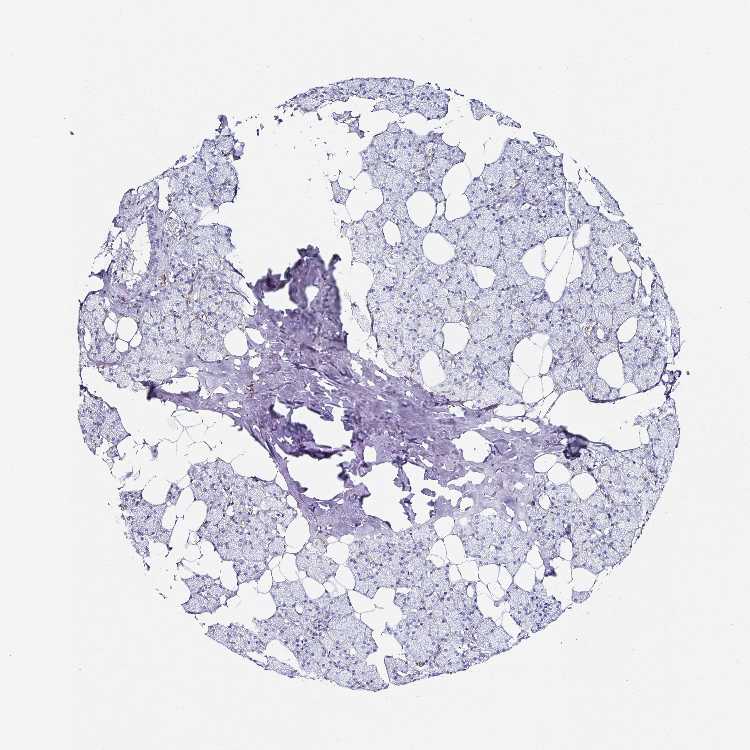

TISSUE PRIMARY DATA SALIVARY GLAND Show tissue menu

SALIVARY GLAND - Antibody stainingi

Antibody staining in the annotated cell types in the current human tissue is reported as not detected, low, medium, or high, based on conventional immunohistochemistry profiling in selected tissues. This score is based on the combination of the staining intensity and fraction of stained cells.

Each image is clickable and will lead to virtual microscopy that enables deeper exploration of all samples and also displays staining intensity scores, fraction scores and subcellular localization as well as patient and tissue information for each sample.

Antibody HPA053419Antibody HPA054132

Glandular cells Not detectedNot detected